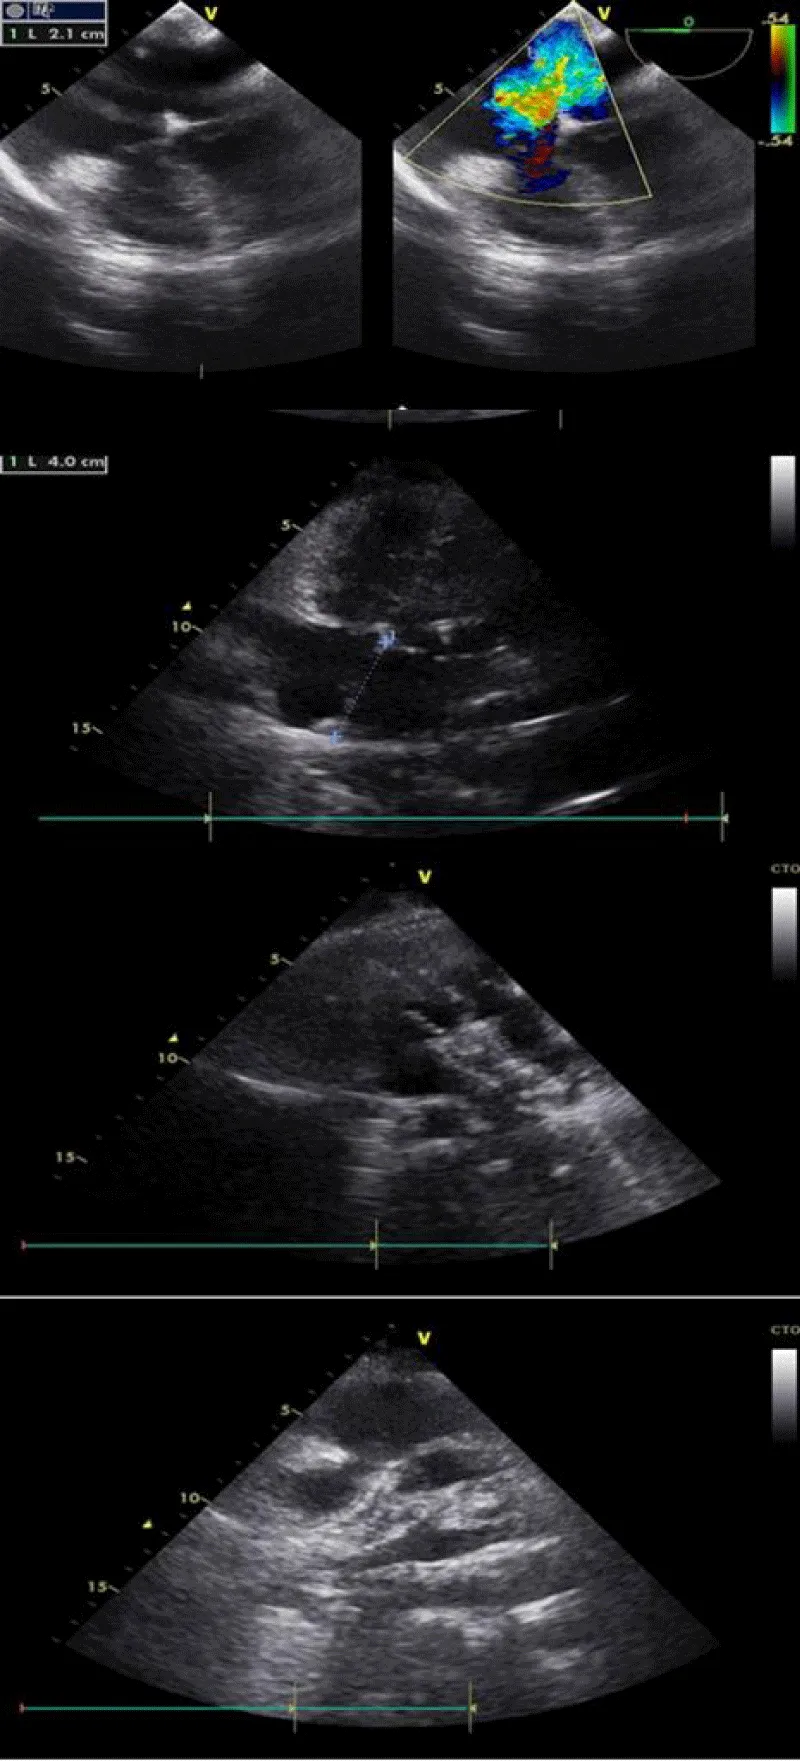

Faced with the desire for pregnancy and with this right cavitary impact and the existence of satisfactory edges (retro-aortic edge 9 mm, posteroinferior edge 10mm, atrioventricular edge 10 mm, upper edge 9 mm, lower cave edge 10 mm, upper cave edge 12 mm) her treating cardiologist decides to entrust her to us for percutaneous closure of this defect (Figure 1).

Figure 1: ASD evaluation before the percutaneous procedure. (A: Right cavities dilatation, B: Tricuspid regurgitation, C-D and E: ASD and edges in TTE, F-G, and H: ASD and edges in TEE).